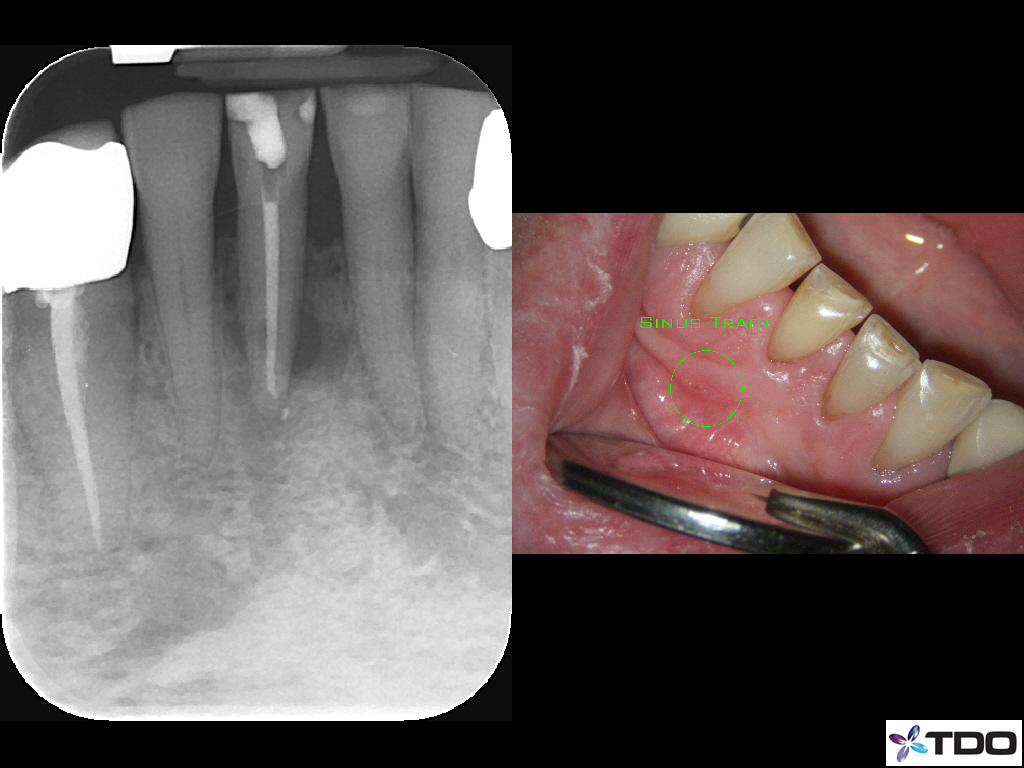

Blog Image